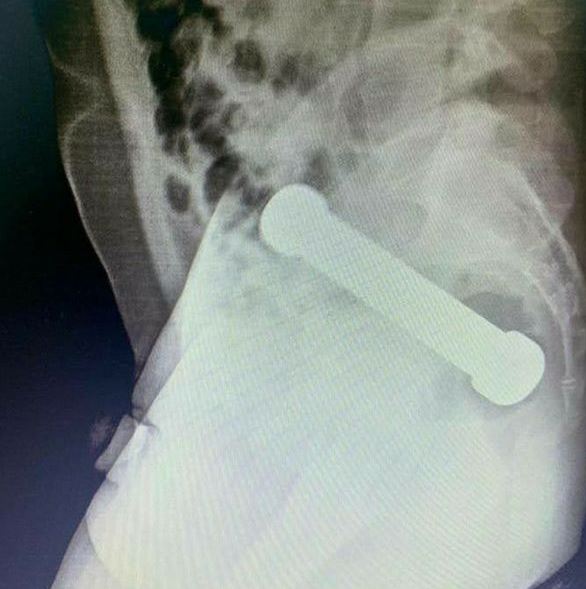

An eight-inch dumbbell, weighing 2kg, has been removed from the rectum of a 54-year-old man after he arrived at A&E complaining of cramps and severe constipation.

Medics said the patient was "uncooperative" while he was being examined, so they decided to X-ray his abdomen.

They then found an object, that was later revealed to be a 2kg dumbbell, lodged firmly in the 54-year-old man’s rectum.